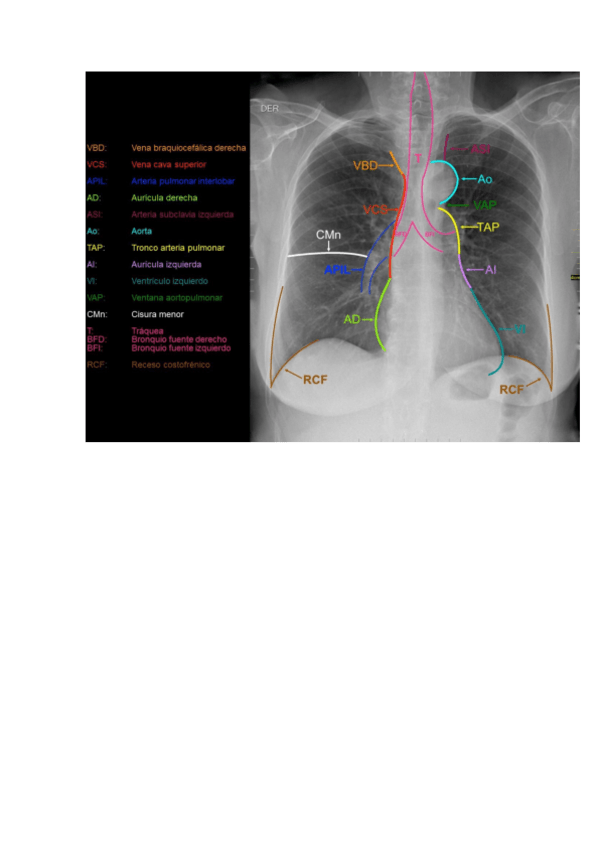

5 - Aparatos circulatorio y respiratorio

He publicado nuevos apuntes de Anatomía por la imagen: 5 - Aparatos circulatorio y respiratorio

Estructuras-del-mediastino.pdf